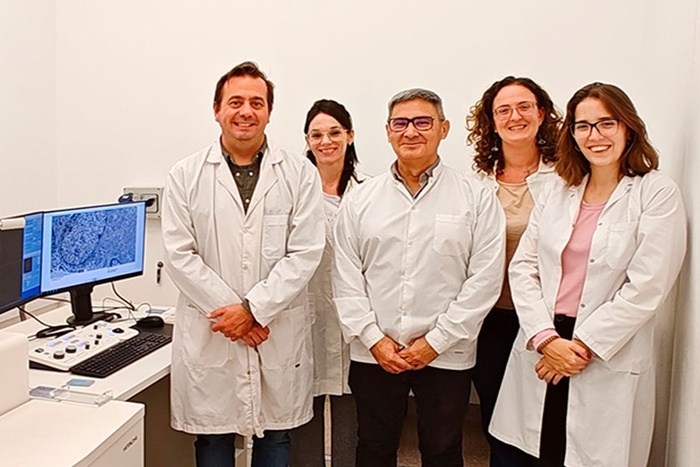

Juan Pablo Petiti, investigador del CONICET, y Gilda Mezger, becaria del CONICET, analizando células tumorales en un microscopio de alta resolución.

Juan Pablo Petiti, Liliana Sosa, Natacha Zlokowski, Gilda Mezger y Erica Faure, del INICSA (CONICET-UNC), con médicos del Hospital Privado Universitario de Córdoba: Laura Anahí Cecenarro, Juan De Battista y Patricia Calafat.